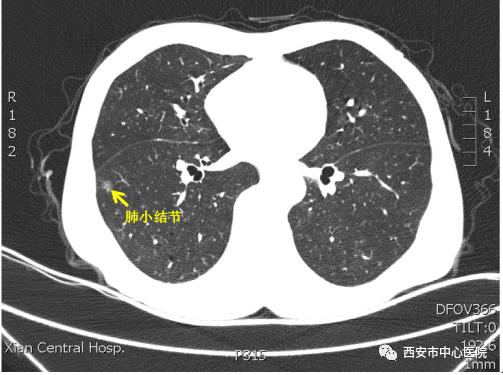

据文献报道约10%-20%肺部小结节是恶性肿瘤。针对这些肺小结节,特别是磨玻璃结节,传统的检查手段如穿刺活检、支气管镜、PET-CT等对于“痘痘”的良恶性无法穿刺定性或“痘痘”太小不易穿刺,辨识度也不清楚,而带鱼钩的肿瘤穿刺定位针是解决上述盲点的精准手段,对以后的诊断及治疗有着重要意义。

近日市中心医院胸外科联合放射科应用肺结节定位针对肺小结节进行术前精准定位,然后成功完成了一例单操作孔胸腔镜下肺小结节切除术。

患者为一名62岁男性,因咳嗽4月来我院就诊,行胸部CT发现左下肺磨玻璃结节大小约8.6cm×7.7cm。由我院李建英副院长领衔的肺小结节MDT专家团队对患者肺小结节进行了综合评估,根据胸部CT上肺结节的影像特征(>8mm磨玻璃结节),结合患者慢性咳嗽等临床症状,认为此患者肺小结节为早期肺癌可能性大,建议患者手术治疗。

患者入住我院胸外科后,徐涛主任团队为患者制定了术前定位针精确定位联合单操作孔胸腔镜微创手术的治疗方案。这种方法是目前治疗肺部小结节最前沿最有效的方案。首先在放射科医师的辅助下进行CT下定位,医生将肺结节定位针进行精准定位并将定位针留置在小结节的位置上,定位完成后,患者直接被送往手术室,由徐涛主任主刀,李广顺主治医师为一助,成功完成了单操作孔下胸腔镜微创肺肿瘤切除。白娟护士长带领的护理团队为其定制术后快速康复计划:患者于术后6小时开始胸外专科功能锻炼,14小时下床活动,术后第3天拔除胸管,5天后康复出院。术后的早期活动极大地降低了深静脉血栓的发生率,降低了患者的住院时间和经济压力。